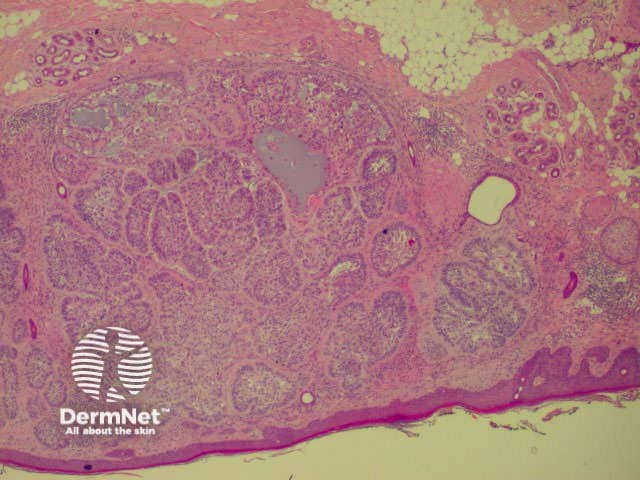

Invasive squamous cell carcinoma (SCC) is characterised by dermal invasion. Link to a clinical description of invasive squamous cell carcinoma.

SCC is characterised by proliferation of irregular nests of abnormal squamous cells arising from the epidermis and invading the dermis. Tumours are traditionally divided into well, moderately or poorly differentiated tumours by a subjective assessment of how significantly the tumour cells differ from normal keratinocytes. In general, the greater the degree of keratinization, the better differentiated the tumour is thought to be. Except in the case of very poorly differentiated tumours, this does not have a great bearing on prognosis. More important is the depth and irregularity of invasion, particularly the presence of perineural infiltration, which is associated with a much higher rate of recurrence if not widely excised. The site of the lesion is also important; tumours of the lips and ears have a considerably higher rate of metastasis to lymph nodes.

There are several descriptive variants of SCC including spindle cell SCC and acantholytic (or adenoid or pseudoglandular SCC). These mainly are of note due to the difficulty of diagnosing the tumour as SCC, but they may also imply a slightly worse prognosis. A further rare variant is verrucous carcinoma, a lesion in which the histology has a deceptively benign appearance in that there is very little cytological abnormality. Diagnosis in these cases may be delayed and the diagnosis may not be made until several biopsies have been performed. These tumours recur locally, but do not generally metastasise.

From the above comments it can be seen that the histological features of SCCs can vary, but in general are:

Pathology of SCC Pathology of SCC Pathology of SCC Pathology of SCC